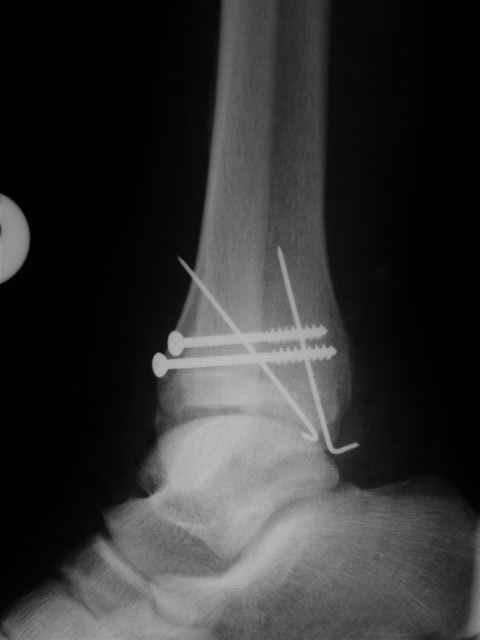

> интересуюсь тактикой лечения повреждений голеностопного сустава.

Ничего сверхъестественного, но если есть интерес, то в понедельник пересниму Рг-граммы и отправлю.

Уважаемый Иван,

Я предупреждал, что ничего сверхъестественного. Каюсь, что одна из спиц прошла несколько дальше, чем нужно было, но главное - перелом стабилизирован и больной работает суставом в полном объёме, несмотря на представленную раннее травму коленного сустава.